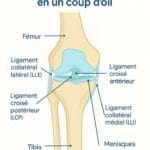

Lésions méniscales ou ligamentaires non traitées

Une lésion du ménisque, même ancienne, peut se réveiller en position allongée. Le genou devient douloureux lors d’un mouvement involontaire la nuit. Les douleurs ligamentaires post-traumatiques sont aussi fréquentes après une entorse mal soignée.

Imagerie : IRM, radio, échographie

- Radiographie standard : utile pour diagnostiquer l’arthrose.

- IRM : détecte les lésions ligamentaires ou méniscales.

- Échographie : évalue les bursites ou tendinites.